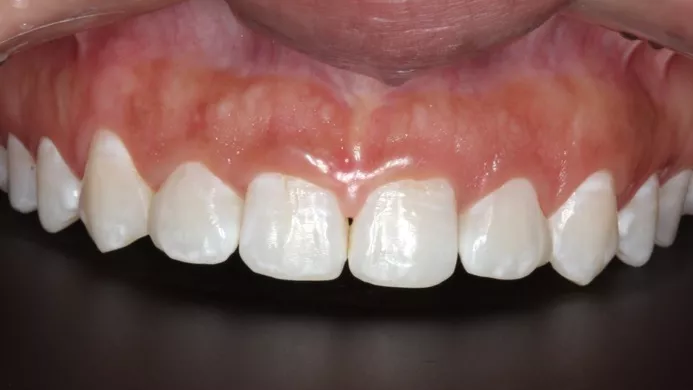

Guided rehabilitation with implant in upper incisors region, after loss due to root resorption